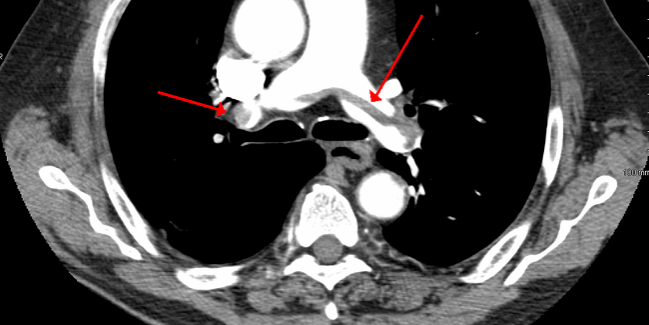

The type of ct scan your doctor orders will depend in large part on the area of the body they want to evaluate. Computed tomography (ct) scanning is used commonly in medicine today. The scan is painless and takes about 10 to 30 minutes. Ct scans of the abdomen may also be used to visualize placement of needles during biopsies of abdominal organs or tumors or during aspiration (withdrawal) of fluid from the abdomen. Ct scan of the abdomen. For example, ct has become a useful screening tool for detecting possible tumors or lesions within the abdomen. This provides a series of images from many different angles. When ct scans are used.

The arrow indicates the superior mesenteric artery. A ct scan allows for more insightful analyses than other imaging tests without the need for invasive over 70 million ct scans are performed in the united states each year, according to research from. Computerized tomography (ct scan) is a procedure that assists in diagnosing tumors, fractures, bony structures, and infections in the organs and tissues of the body. It usually takes approximately 10 to 30 minutes to. Ct scan of the abdomen. What is the difference between ct scan vs mri scan. How do ct scans work? Image slices that ct scans produce can. Ct scans can produce detailed images of many structures inside the body, including the internal organs, blood vessels and bones. The type of ct scan your doctor orders will depend in large part on the area of the body they want to evaluate. Ct scans are most often an outpatient procedure. The person lies on a table that moves through a scanning ring, which looks like a large doughnut. A tumor is visible in the head of the pancreas.

A ct scan can help doctors find cancer and show things like a tumor's shape and size.